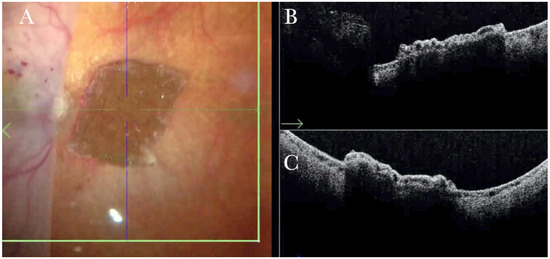

(A) Microscope view of the macular area with an epiretinal membrane (ERM) after staining with Doubledyne blue. (The white box indicates the field-of-view of the OCT scan, the green circle within the white box represents the effective working distance and green and blue lines within the green circle show the vertical and horizontal scan planes). (B) Intraoperative optical coherence tomography (i-OCT) B horizontal (green arrow) scan showing the macular profile after peeling and restaining with Doubledyne blue. (C) i-OCT B vertical (blue arrow) scan showing the macular profile after peeling and restaining with Doubledyne blue.

In primary ERMs, the i-OCT was as satisfactory as the dye staining in visualizing both the ERM (Figure 1) and the ILM (Figure 2), and enhancing well the visualization of the dynamic of the staining (Figure 3) and the membranes with architectural changes after the peel. The i-OCT was visualized when the ERM and the ILM were peeled simultaneously (Figure 4).